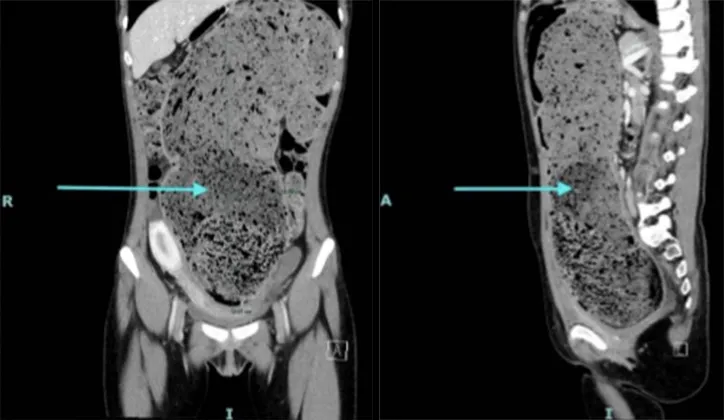

Kasus tersebut kemudian ditangani tim medis yang menemukan usus besar pasien memiliki ukuran abnormal. Ususnya melebar hingga 15 sentimeter dan penuh dengan tinja yang sudah lama mengeras.

Temuan medis itu dicatat dalam laporan yang dipublikasikan di jurnal Cureus. Dokter menggambarkan betapa sulitnya melakukan tindakan pemeriksaan karena tinja pasien terlalu padat dan keras.

"Pada bagian distal kolon sigmoid, endoskopis tidak dapat melanjutkan kolonoskopi karena keterbatasan visibilitas akibat tinja yang keras, dan tidak ada upaya pelunakan dengan lavage yang mampu menggerakkan tinja tersebut," tulis laporan tersebut, dikutip brilio.net dari The Sun, pada Rabu (3/9).

Dokter yang menangani juga menyebut prosedur manual tidak bisa dilakukan sepenuhnya. Tinja yang menumpuk sangat keras sehingga penanganan harus dihentikan sementara.

"Selain itu, praktisi tidak dapat menjangkau area tersebut secara manual sehingga prosedur harus dihentikan," lanjutnya.

Kondisi pasien membuat ususnya terlihat membesar secara signifikan. Dokter menggambarkan tekstur tinja yang dikeluarkan menyerupai tanah liat basah dan padat.

"Dokter mencatat usus besarnya mengalami pelebaran yang signifikan dan tinjanya menyerupai tanah liat yang padat/basah," imbuhnya.